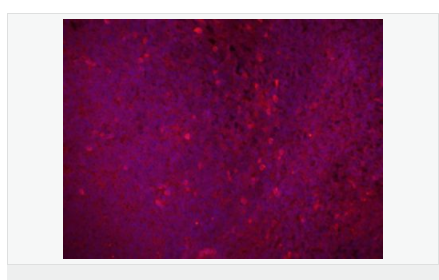

| 產品應用 | WB=1:500-2000 IHC-P=1:100-500 IHC-F=1:100-500 Flow-Cyt=1μg/Test IF=1:100-500 (石蠟切片需做抗原修復) not yet tested in other applications. optimal dilutions/concentrations should be determined by the end user. |

| 產品介紹 | The Bcl-2 gene was isolated at the chromosomal breakpoint of t(14;18)-bearing follicular B cell lymphomas(1,2).Bcl-2 blocks cell death following a variety of stimuli and confers a death-sparing effect to certain hematopoietic cell lines following growth factor withdrawal (3,5).Bcl-2 appears to function in several subcellular locations yet lacks any known motifs that would confer insight into its mechanism of action (6,7).A more recently identified protein,designated Bax p21(i.e., Bcl-associated X protein ),has extensive amino acid homology with Bcl-2 and both homodimerizes and forms heterodimers with Bcl-2(8). Overexpression of Bax accelerates apoptotic death induced by cytokine deprivation in an IL-3 dependent cell line and Bax also counters the death repressor activty of Bcl-2(8). Function: Suppresses apoptosis in a variety of cell systems including factor-dependent lymphohematopoietic and neural cells. Regulates cell death by controlling the mitochondrial membrane permeability. Appears to function in a feedback loop system with caspases. Inhibits caspase activity either by preventing the release of cytochrome c from the mitochondria and/or by binding to the apoptosis-activating factor (APAF-1). Subunit: Forms homodimers, and heterodimers with BAX, BAD, BAK and Bcl-X(L). Heterodimerization with BAX requires intact BH1 and BH2 motifs, and is necessary for anti-apoptotic activity. Interacts with EI24 (By similarity). Also interacts with APAF1, BBC3, BCL2L1, BNIPL, MRPL41 and TP53BP2. Binding to FKBP8 seems to target BCL2 to the mitochondria and probably interferes with the binding of BCL2 to its targets. Interacts with BAG1 in an ATP-dependent manner. Interacts with RAF1 (the 'Ser-338' and 'Ser-339' phosphorylated form). Interacts (via the BH4 domain) with EGLN3; the interaction prevents the formation of the BAX-BCL2 complex and inhibits the anti-apoptotic activity of BCL2. Interacts with G0S2; this interaction also prevents the formation of the anti-apoptotic BAX-BCL2 complex. Subcellular Location: Mitochondrion outer membrane; Single-pass membrane protein. Nucleus membrane; Single-pass membrane protein. Endoplasmic reticulum membrane; Single-pass membrane protein. Tissue Specificity: Expressed in a variety of tissues. Post-translational modifications: Phosphorylation/dephosphorylation on Ser-70 regulates anti-apoptotic activity. Growth factor-stimulated phosphorylation on Ser-70 by PKC is required for the anti-apoptosis activity and occurs during the G2/M phase of the cell cycle. In the absence of growth factors, BCL2 appears to be phosphorylated by other protein kinases such as ERKs and stress-activated kinases. Phosphorylated by MAPK8/JNK1 at Thr-69, Ser-70 and Ser-87, wich stimulates starvation-induced autophagy. Dephosphorylated by protein phosphatase 2A (PP2A). Proteolytically cleaved by caspases during apoptosis. The cleaved protein, lacking the BH4 motif, has pro-apoptotic activity, causes the release of cytochrome c into the cytosol promoting further caspase activity. Monoubiquitinated by PARK2, leading to increase its stability. DISEASE: Note=A chromosomal aberration involving BCL2 has been found in chronic lymphatic leukemia. Translocation t(14;18)(q32;q21) with immunoglobulin gene regions. BCL2 mutations found in non-Hodgkin lymphomas carrying the chromosomal translocation could be attributed to the Ig somatic hypermutation mechanism resulting in nucleotide transitions. Similarity: Belongs to the Bcl-2 family. SWISS: P49950 Gene ID: 596 Database links: Entrez Gene: 596 Human Entrez Gene: 12043 Mouse Omim: 151430 Human SwissProt: P10415 Human SwissProt: P10417 Mouse Unigene: 150749 Human Unigene: 257460 Mouse Unigene: 9996 Rat Important Note: This product as supplied is intended for research use only, not for use in human, therapeutic or diagnostic applications. Bcl-2基因是指B-cell lymphoma gene。人體濾泡B細胞淋巴瘤中過量表達的原癌基因。由于染色體t(14;18)易位,將Bcl-2基因置于免疫球蛋白重鏈的轉錄調控下,使其表達失控。在細胞系中其過量表達能延長細胞存活期而不誘導細胞增殖。它是哺乳動物中細胞調亡的抑制基因。參與細胞凋亡的調控。腫瘤中的Bcl-2基因可提高侵潤性瘤細胞的生存能力。主要用于濾胞型淋巴瘤、毛細管性白血病及細胞凋亡等方面的研究。 目前研究認為:Bcl-2也是細胞凋亡的一種抑制因子、參與細胞凋亡調控,可以用于各種惡性腫瘤的細胞凋亡的研究。 |